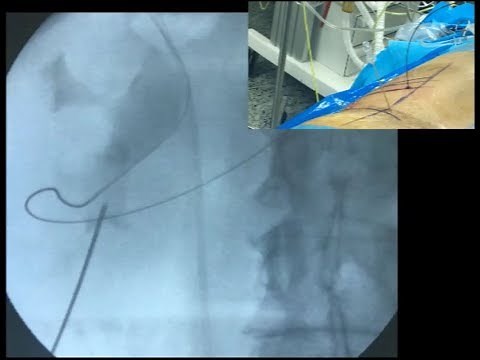

PCNL Access with Fluoroscopy Triangulation Technique

European Association of

已浏览 7.6万 次

2017年9月14日

3:20

YouTube

European Association of Urology